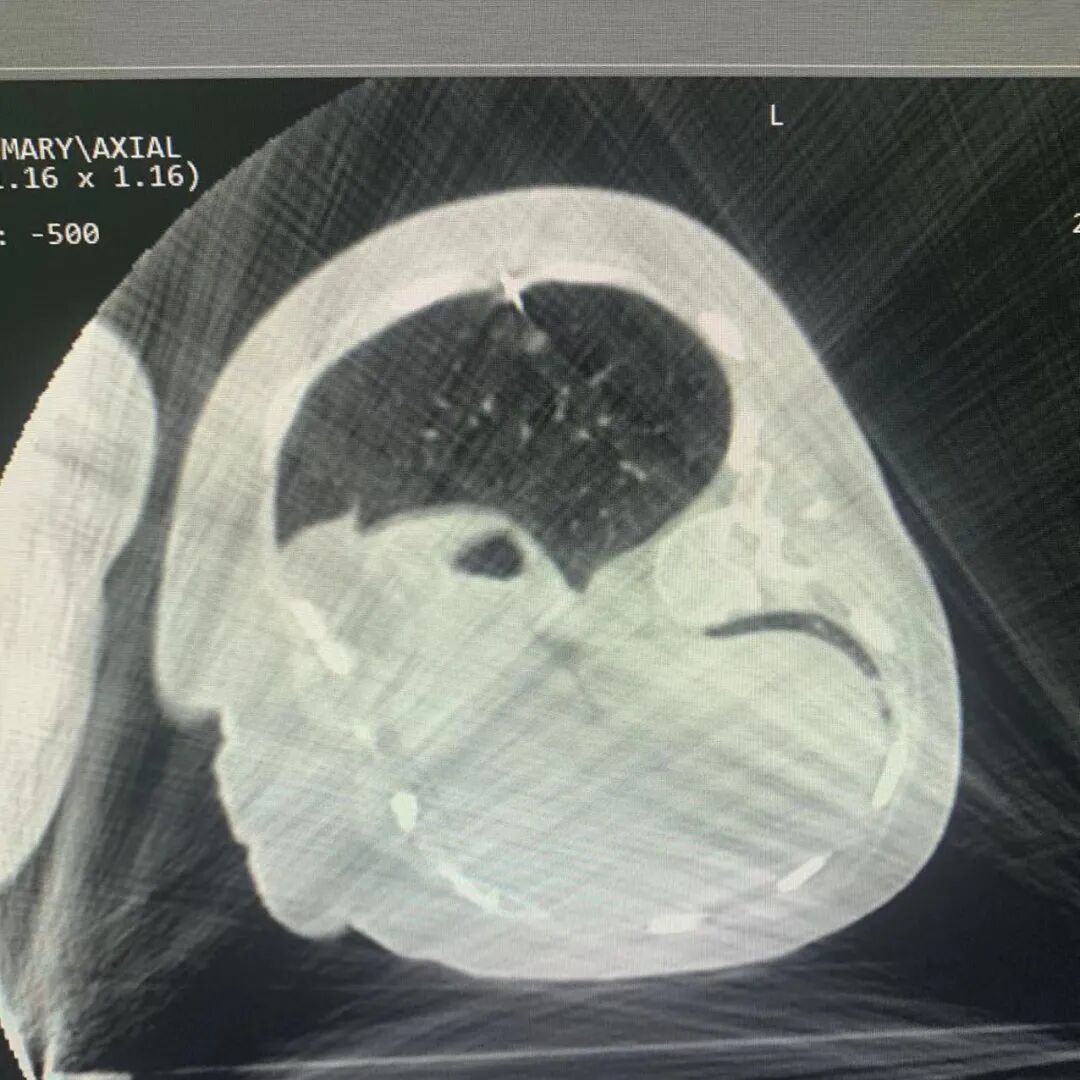

“杂交手术室”是英文“hybrid operation room”的直译,更准确的称呼是复合手术室,可以同时进行外科手术、介入治疗和影像检查。“一站式” 杂交手术在手术时间、 手术疗效与传统手术无差异的情况下,以求取得一加一大于二的效应。病人不需要在手术室之间转移,也不需要多次麻醉,大大降低了手术风险和术后并发症。 ▲BodyTom自由移动CT ▲杂交手术室 “肺小结节”作为肺癌的早期表现,随着健康查体的推广,检出率逐年升高。而肺小结节定位是胸外手术精准切除的关键,胸部微创外科已开展三维成像定位,体表标志定位,气管镜lung-pro染色定位,CT导向下的肺穿刺定位等相关方法。 本次杂交手术中开展的“移动CT”术中定位优点突出。效果良好,气管插管后,肺膨胀状态下,可暂停通气,定位针无移位,定位准确。术中一次麻醉,麻醉后减少患者紧张不适,不变化场地,减少患者转运相关意外发生,不更换气管插管,减少气管刺激,不改变体位,简化手术流程,缩短手术时间。 本例手术是山东省公共卫生临床中心利用移动CT协助完成的第一例胸外科手术,充分发挥了移动CT便捷、精准以及荧光胸腔镜微创的优势,为中心肺小结节精准切除提供又一新选择。胸部微创外科将以此例手术的成功开展为契机,继续发挥院内MDT优势、跨专业技术合作的优势,探索新技术,拓展新业务,不忘初心,勇毅前行,勇攀胸外科专业高峰。